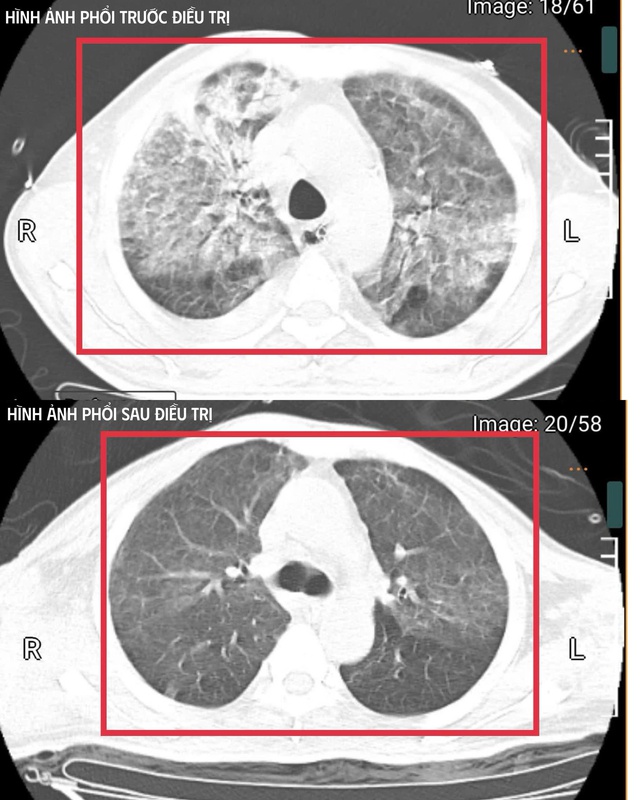

Phổi bệnh nhân trước và sau điều trị (ảnh BVCC).

Sau khoảng ba ngày hồi sức cao độ, bệnh nhân bắt đầu cắt sốt, các chỉ số viêm giảm dần, huyết áp ổn định hơn với nhu cầu vận mạch giảm, chức năng gan thận cải thiện, tri giác dần hồi phục. Người bệnh cai được thở máy qua mở khí quản, tập lại hô hấp tự nhiên và phục hồi vận động.